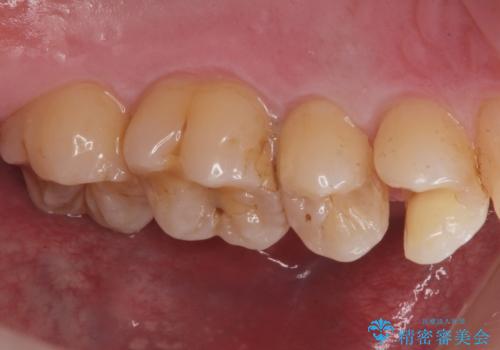

歯と歯の間の虫歯(コンタクトカリエス)

拡大鏡下で虫歯を全て除去して、e-maxインレーにて治療しました。

- e-maxインレー 7.7万円 費用は治療当時の料金となります

コンタクトカリエスについて

コンタクトカリエスは歯と歯の間にできる虫歯で

歯ブラシでは磨くことはできません。

毎日歯間ブラシやフロスを使用することにより予防することができます。